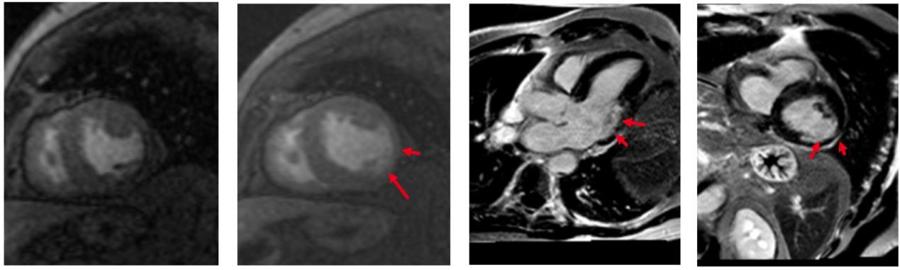

04自由心脏成像平台

传统的磁共振扫描心脏时对病人的心率和呼吸有极高的要求,扫描难度大。新设备配置了生命感知系统,可以实现全新的生命感知自由心脏成像。病人进行心脏扫描时,无需配套任何呼吸门控装置,在扫描过程中,磁共振会全程监测病人呼吸以及心电信号,实时控制信号采集,可以实现业界最快的心脏电影成像,比常规心脏电影成像快10-20倍,可以自由呼吸状态,一个心动周期完成电影采集。

心肌缺血伴部分心肌损伤患者的心脏MRI

心肌缺血患者的心脏MRI